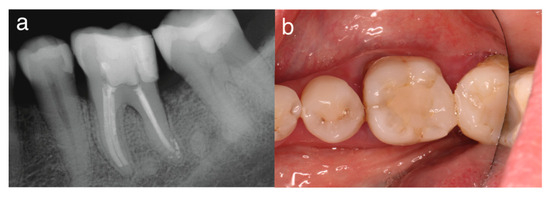

Objective: To report a rare case of pulp space tissue growth in a mature mandibular molar with severe endo-periodontal involvement after conservative endodontic treatment and to discuss the possible biological explanations, including regeneration and granulation tissue healing. Severe endo-periodontal lesions are challenging, particularly [...] Read more.

Objective: To report a rare case of pulp space tissue growth in a mature mandibular molar with severe endo-periodontal involvement after conservative endodontic treatment and to discuss the possible biological explanations, including regeneration and granulation tissue healing. Severe endo-periodontal lesions are challenging, particularly as endodontic regeneration is usually observed in immature teeth, while revascularization in mature teeth, especially in cases of advanced periodontal disease, is rare, as demonstrated in this case. Methods: This study reports a rare case of tissue regeneration versus granulation tissue healing in the pulp space, occurring alongside periodontal healing, in a mature mandibular molar with necrotic pulp and severe periodontal involvement. A 52-year-old patient presented with a mature mandibular molar (tooth #19) exhibiting necrotic pulp with severe endo-periodontal involvement, including grade-3 mobility, tenderness to percussion, a 12 mm probing depth, and extensive periradicular radiolucency. The tooth was diagnosed with necrotic pulp and symptomatic apical periodontitis and was deemed hopeless, with extraction planned. Results: Following patient refusal, endodontic treatment was initiated, including cleaning, shaping, and placement of the intracanal medicament, Ledermix. The patient canceled the extraction due to symptom resolution and disappeared for 12 months. On return, the patient presented with spontaneous pain exacerbated by thermal stimuli, consistent with symptoms of irreversible pulpitis. Clinical examination revealed significant clinical and radiographic improvements, including reduced probing depth (3 mm), no mobility, resolution of apical translucency, radiographic findings suggestive of canal narrowing, and a positive pulp sensibility response. Re-entry elicited profuse bleeding with newly formed vital tissue beneath the medicament. Sodium hypochlorite irrigation failed to achieve hemostasis; inflamed tissue was removed; root canals were cleaned, shaped and obturated; and treatment was completed with placement of a permanent coronal resin composite restoration. A forty-month follow-up showed an asymptomatic tooth with clinical and radiographic healing. Conclusions: This case demonstrates that conservative endodontic management may result in favorable clinical and radiographic outcomes in mature teeth with severe endo-peroidontal involvement, influencing extraction decisions. It provides clinical evidence suggestive of tissue regeneration and periodontal healing in a mature tooth with necrotic pulp and severe periodontal compromise, challenging conventional prognosis. The observed pulp space tissue growth may be suggestive of regeneration; however, alternative explanations, including granulation tissue healing or repair processes, cannot be excluded. Healing by granulation tissue in the pulp space remains possible. Root canal treatment in advanced endo-perio lesions can yield favorable outcomes and may influence extraction decisions. Further clinical and histological studies are needed to clarify underlying mechanisms and optimize treatment strategies. Full article

Show Figures

Figure 1